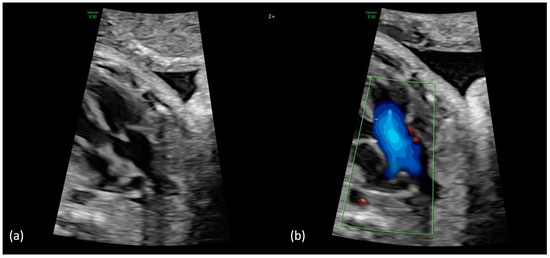

(a,b): Truncus arteriosus type 4 with interrupted aortic arch type b at 23 + 5 weeks. (a) The 2DE shows the ventricular outlet part with the overriding common trunk, the truncal valve as well as the wide truncus pulmonalis and the hypoplastic ascending aorta (pulmonary dominance); (b) The color Doppler mode shows the outflow from both ventricles into the common arterial trunk and further into the pulmonary trunk as well as into the hypoplastic aorta.

Figure 4.